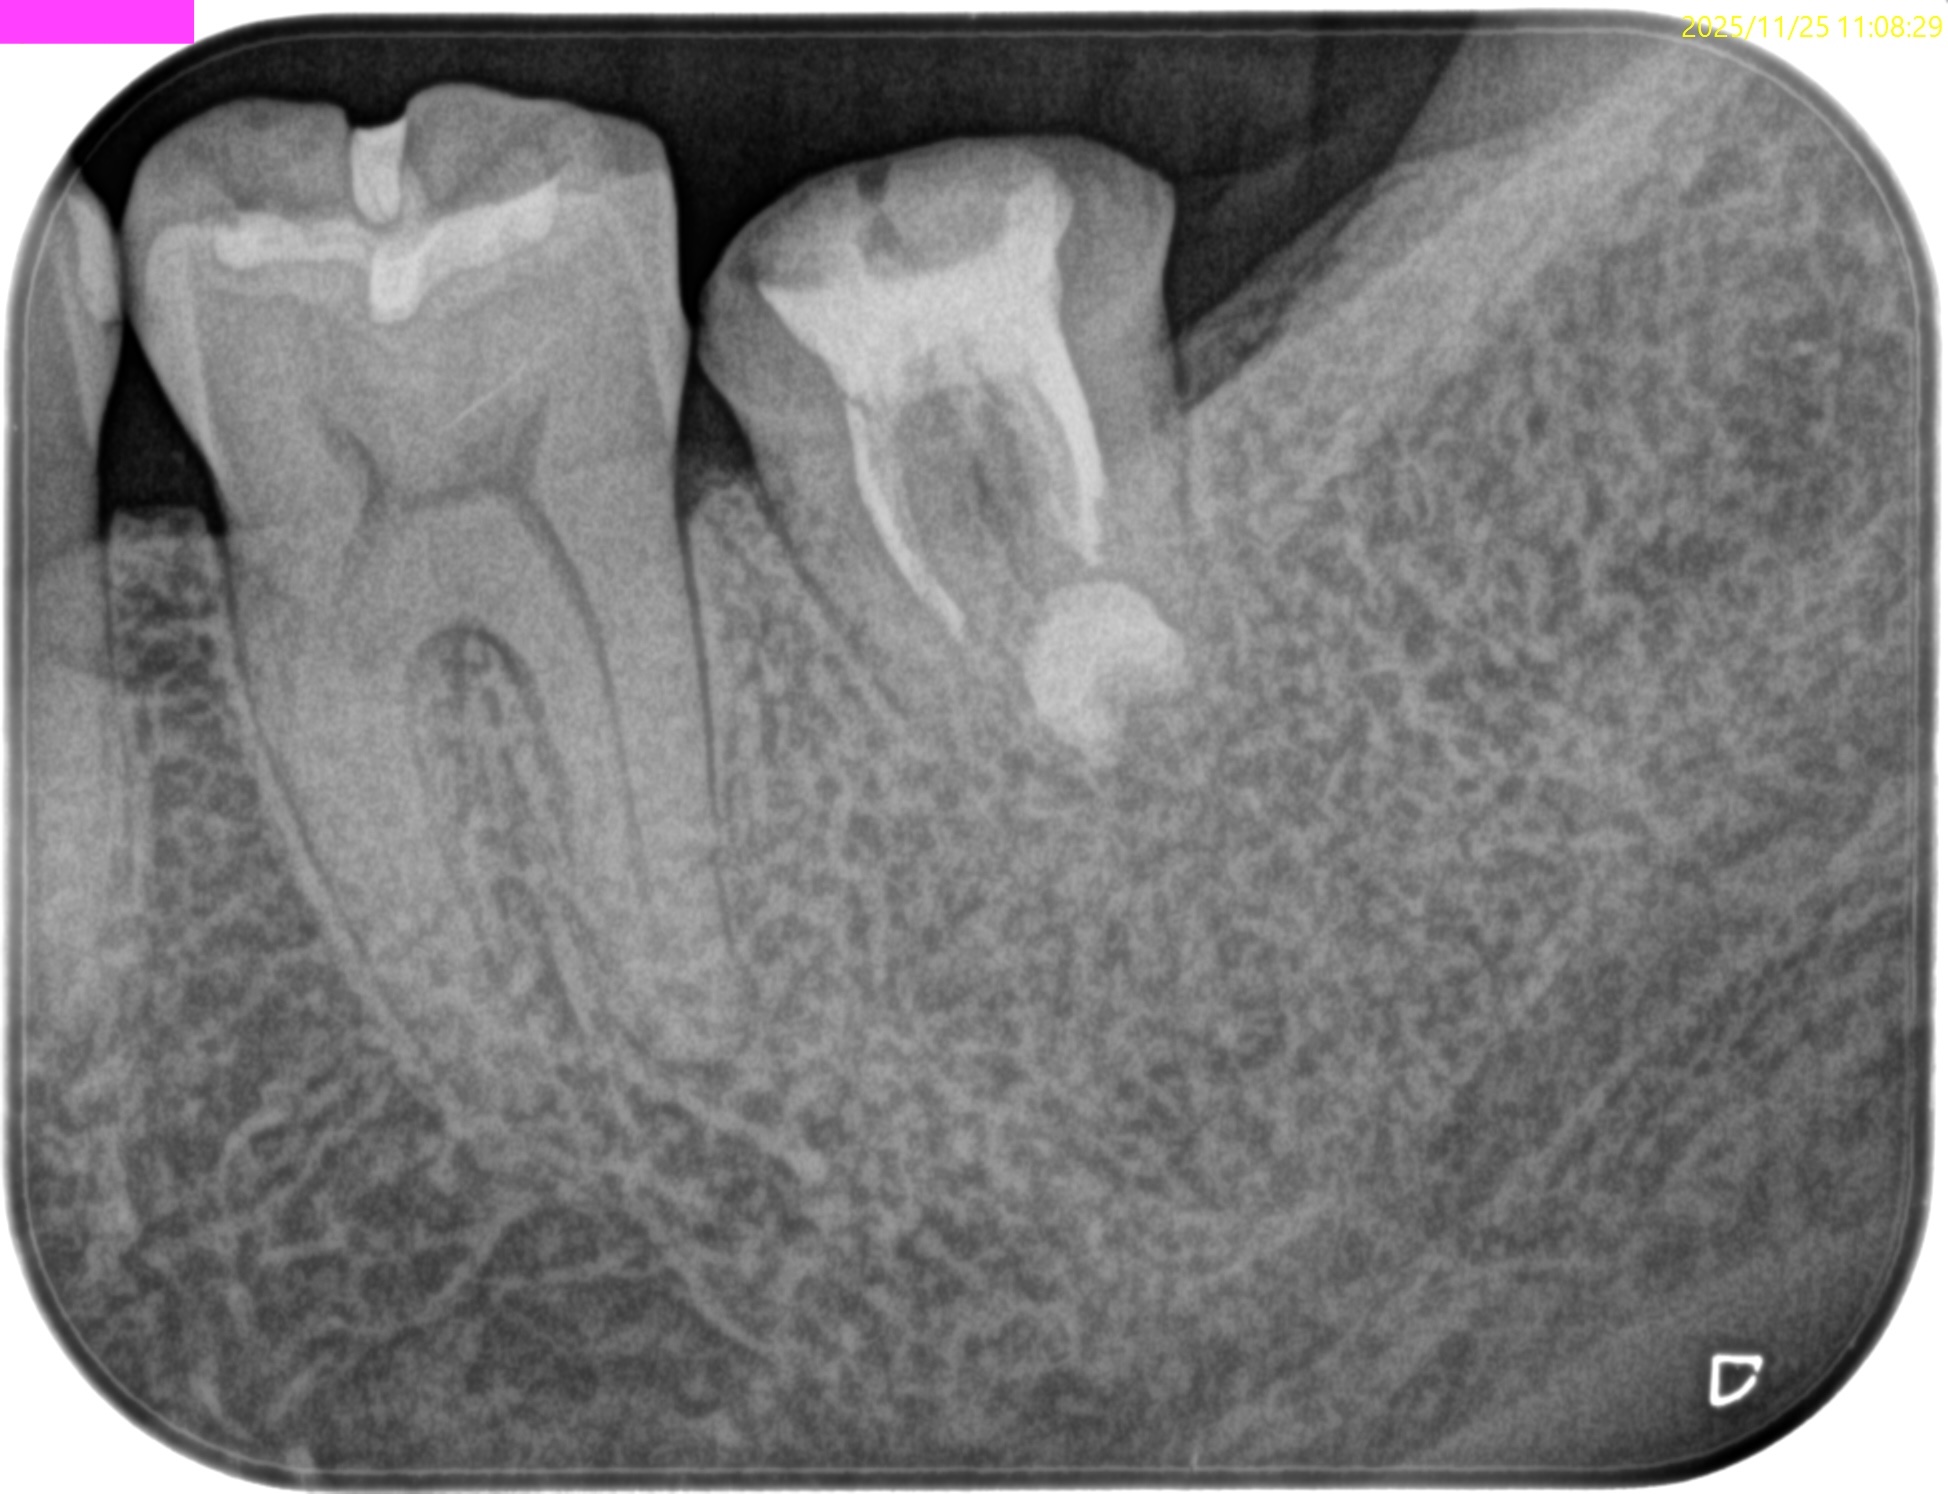

初診時と比較した。

5年前から悩まされていた歯肉の腫脹は消失し、歯槽骨も完治した。